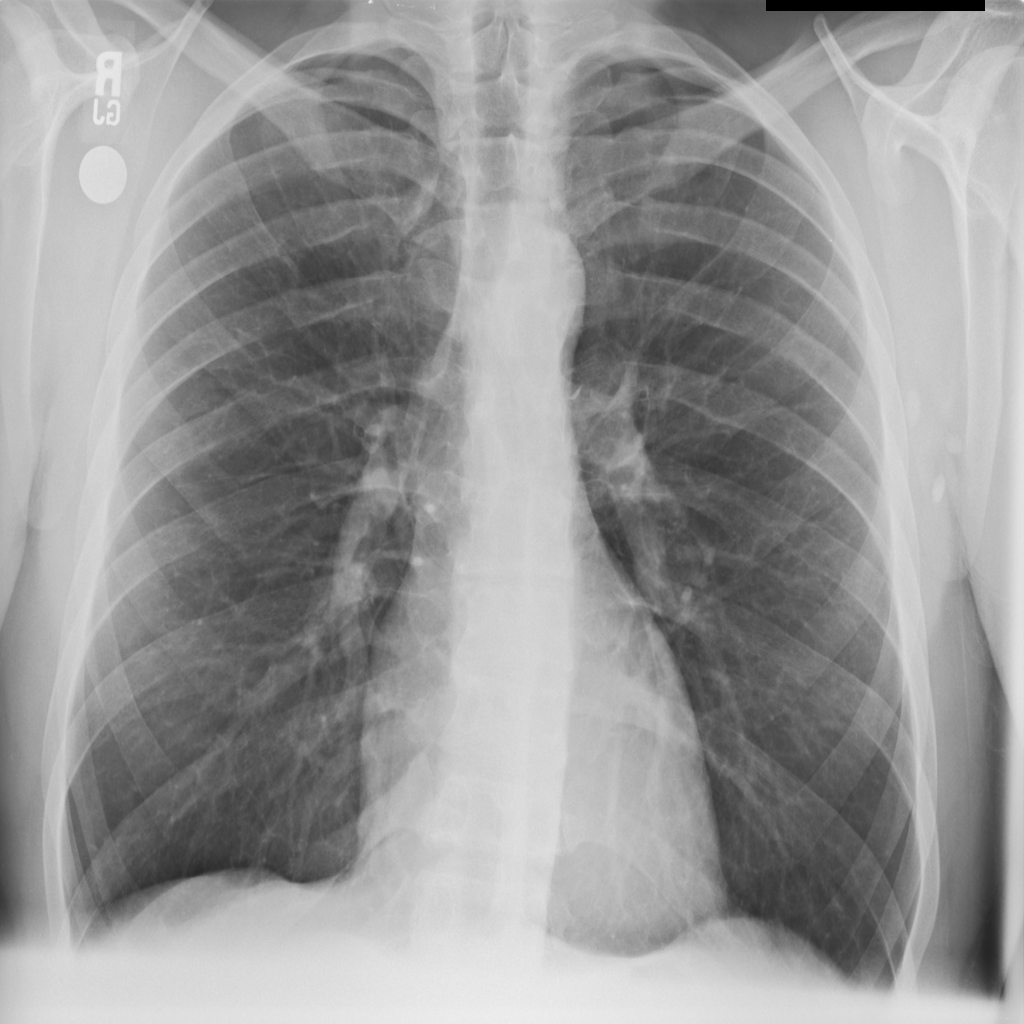

Nodule

A nodule is a small rounded opacity in the lung or chest field. It is a descriptive imaging finding that can be benign or more concerning depending on size, appearance, and context.

Showing up to 90 reference images for Nodule.

PAT-FB8F · IMG-000Nodule

PAT-FB8F · IMG-000

PA